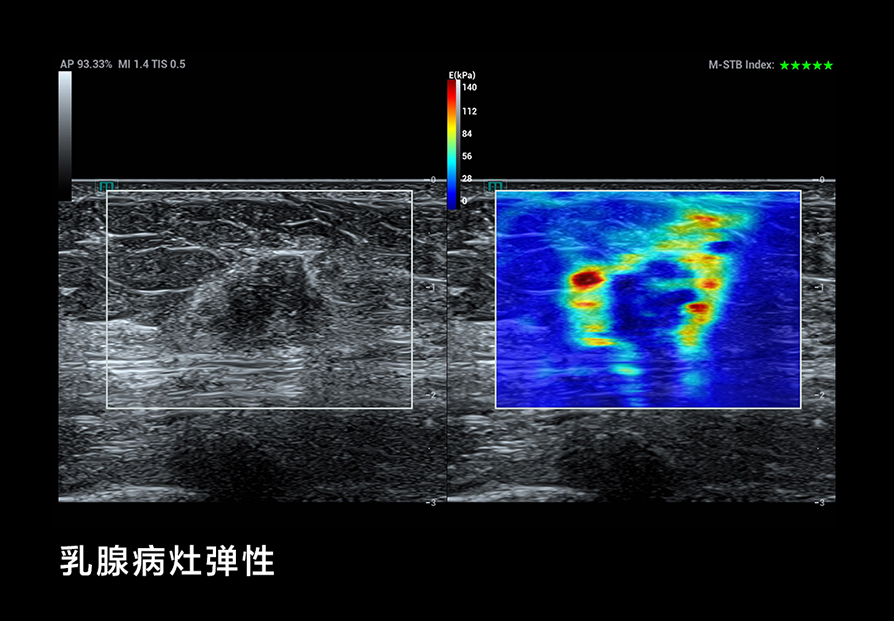

我们在 B-Mode 成像方面考虑了更细(超高频率)、更深(超低频率),更好的对比分辨率,如个异化的 HD Scope,以提高早期鉴别诊断的能力;在超微血流方面, UMA突破传统彩色多普勒的限制,使细微血流的显示达到新的高度;还有创新的血流流变学(VFM)等分析技术,以及流变学与生物力学结合的技术等;在弹性成像方面,我们也有很多可圈可点的地方。我们可以形成多模态,多模式的成像与显示,为临床和科研提供新的工具;在造影成像(CEUS)方面,我们还有极具特色的高帧率造影技术和 CEUS QI 分析系统,还有光声成像等这些新的方向。